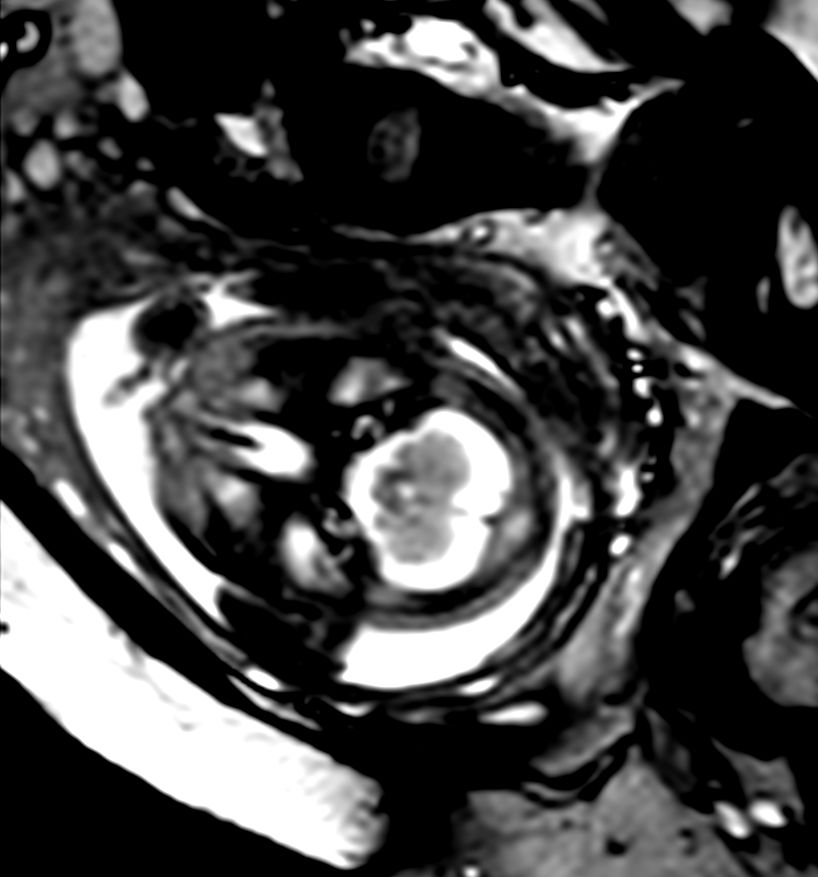

Axial bFFE (IAC)Compressed SENSE